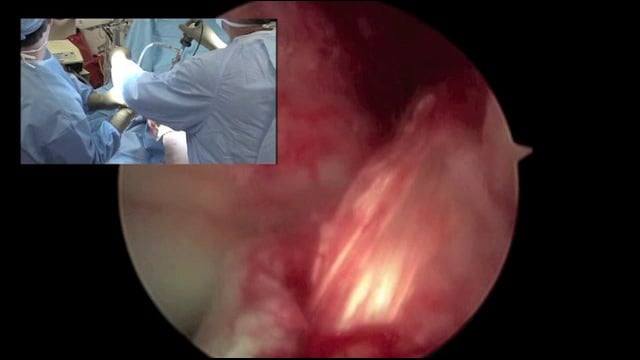

Femoral Physeal Sparing ACL Reconstruction - Dr. Mark Miller

This video demonstrates a Femoral Physeal Sparing ACL Reconstruction performed by Dr. Mark Miller.

Dr. Mark D. Miller is the S. Ward Casscells Professor of Orthopaedic Surgery and the Head of the Division of Sports Medicine at the University of Virginia. He is also the team doctor at James Madison University in Harrisonburg, Virginia. He is nationally and internationally known for his expertise in sports medicine, shoulder surgery and knee surgery. Dr. Miller has published over 100 peer-reviewed articles and 20 textbooks.